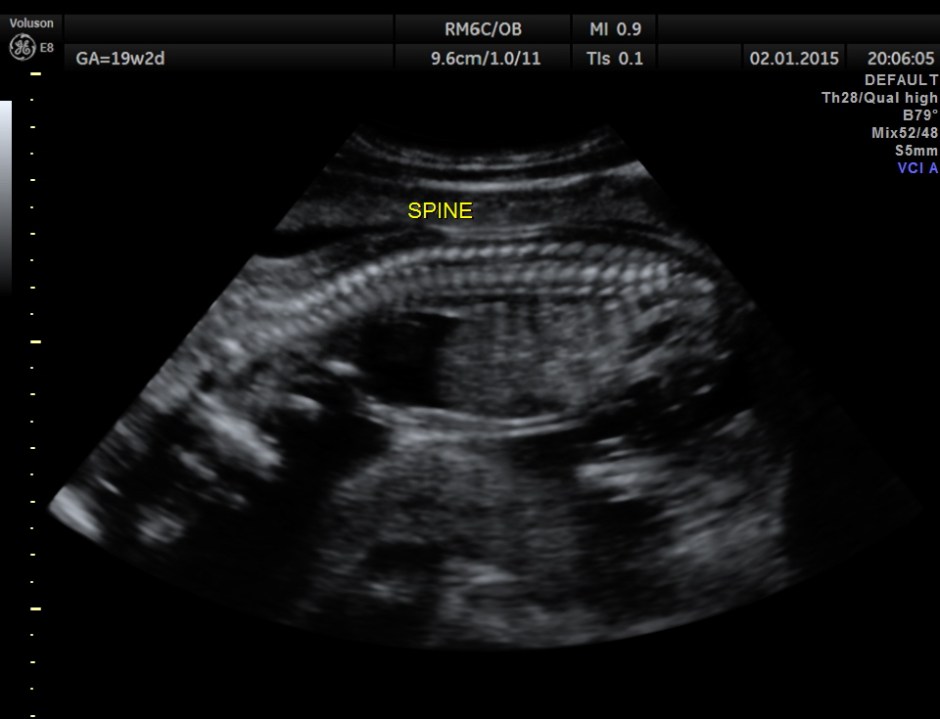

The rest of the scan findings were normal.